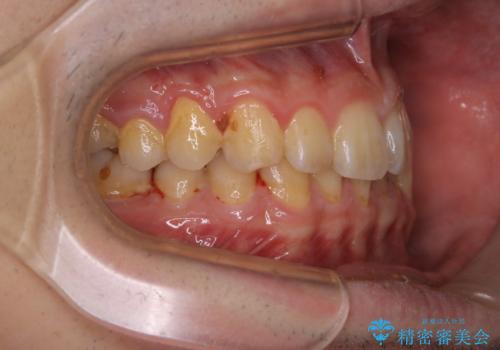

人生で初めてのクリーニングということもあり、プラークや歯石が大量に付いていました。それにより、歯茎の腫れもあり出血も多かったです。これから矯正をスタートしていくため、歯ブラシ指導を行いホームケアを頑張ってもらっています。